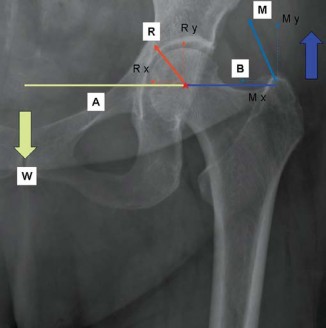

Introduction A primary goal of successful total hip arthroplasty (THA) is to re-establish correct hip biomech…